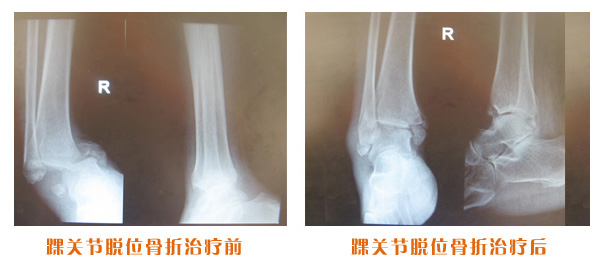

復位前后對比

踝關節脫位骨折治療前后對比